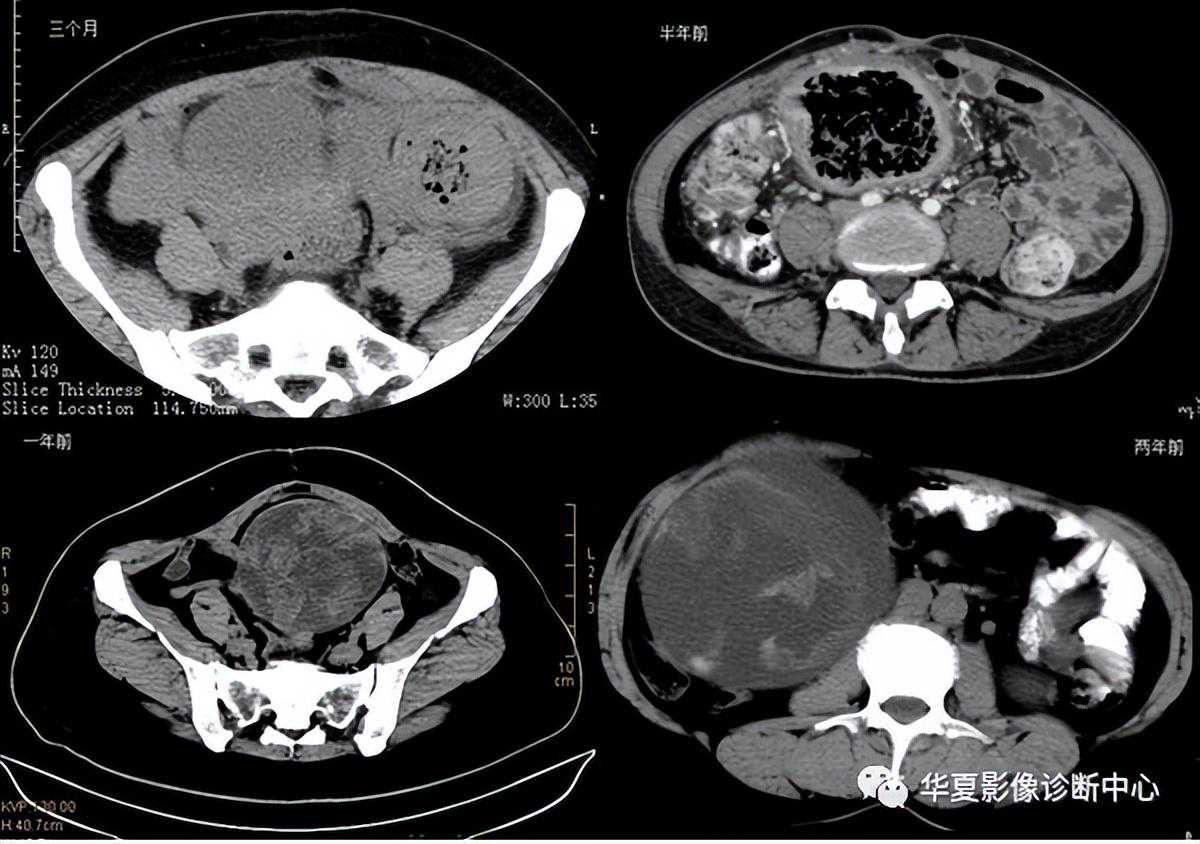

纱布瘤的影像特点是:圆形或卵圆形肿块,较大,有完整包膜,薄壁,较少的情况下为后壁,边界较完整,增强后薄膜可以持续强化。不同时期的纱布瘤可以不同的表现:早期(如10各月或半年前)的多表现为蜂窝状;2~5年内一般表现为囊性飘带状;10~20年之后则为实性软组织密度,包膜钙化呈钙化性网状结构。手术过程中残留在人体内的医用纱布所形成的肿瘤样病变。以下是不同时期纱布瘤的表现: